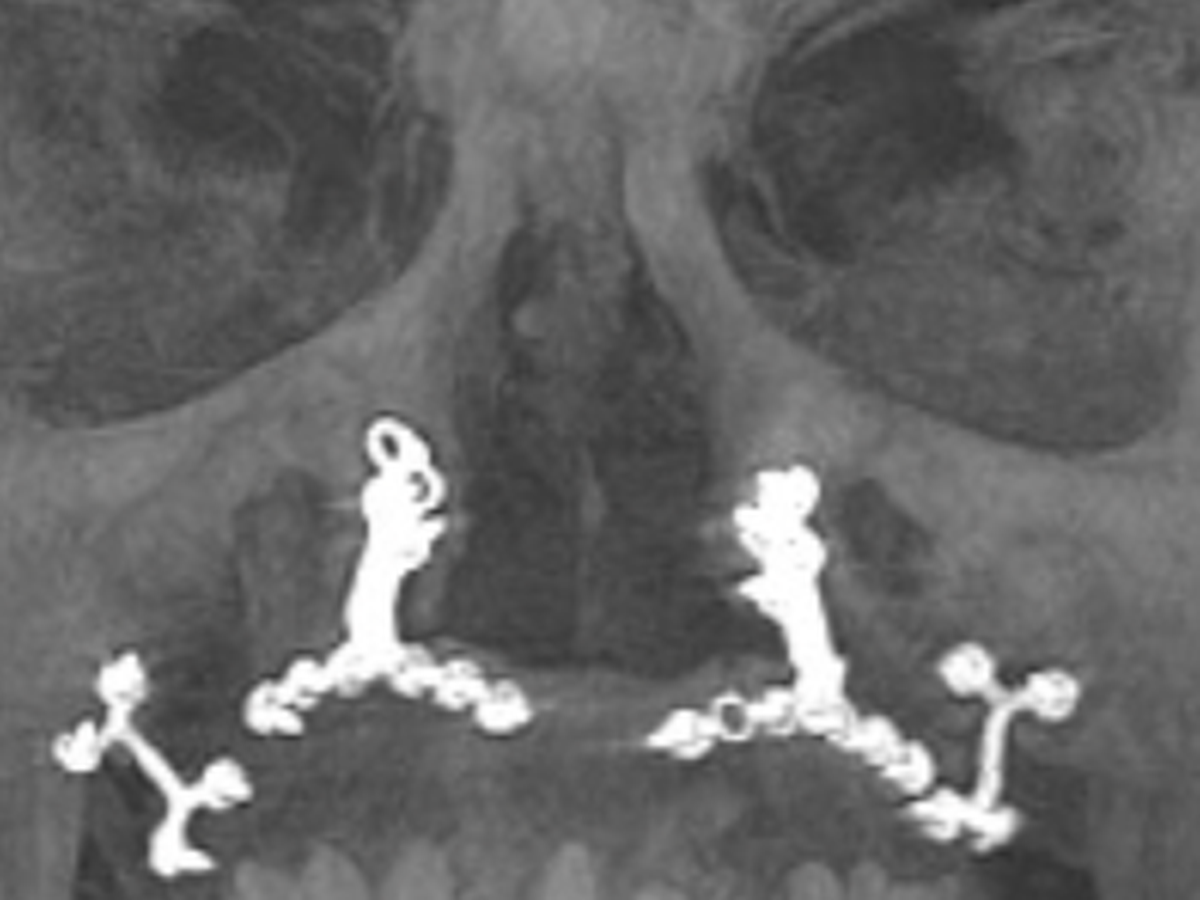

If you're reading this, chances are you know me. My name is Norman Walsh, and I'm reaching out to you for support during a challenging chapter in my life. For those who have knew me 30 years ago, you are likely aware that I survived a devastating car accident that should have claimed my life. I consider myself incredibly fortunate. Thanks to the expertise of skilled surgeons in Boston, I underwent extensive facial reconstructive surgery, which included the insertion of titanium implants to rebuild my jaw, face, and skull. These remarkable procedures, along with the use of one of my ribs to reconstruct my nose, allowed me to reclaim a semblance of normalcy and live a fulfilling life.

However, as time has passed, the effects of the accident have resurfaced. The titanium screws that once held my jaw together have begun to fail. About two years ago, I noticed the screw heads protruding through the roof of my mouth, some eventually fell completely out. Despite the initial success of the surgeries, I now find myself in need of further intervention to address the complications that have arisen. Essentially, the hardware installed 30 years ago has now failed.

Initially, the estimated cost for the necessary surgeries were quoted at $46,000 by the doctor who performed my procedures two years ago. However, I now have found an amazing doctor willing to do it for less,$40,000. This is great news because this doctor is better, and I didn’t really want to go back to the same doctor who installed the currently failing hardware. This new quote includes the full oral surgery needed to restore my health and smile. The surgery will involve the removal of old hardware, multiple bone grafts, a sinus lift, and the insertion of new titanium hardware to hold my jaw together.